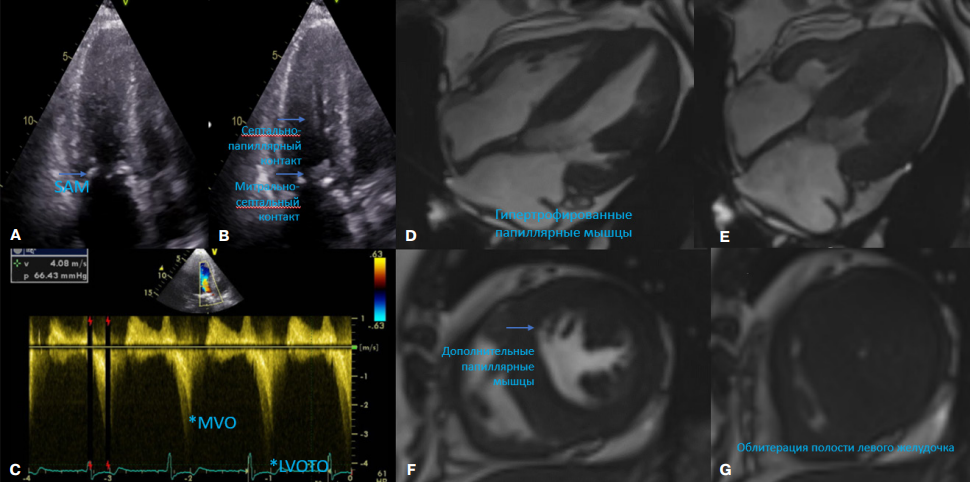

На рисунке 1 представлены данные мультимодальной визуализации сердца пациентки. Многоуровневая обструкция была вызвана незначительным стенозом аортального клапана (peak gradient 20 мм рт.ст., mean gradient 12 мм рт.ст.), выраженной обструкцией ВТЛЖ (66 мм рт.ст.), а также средне-желудочковой обструкцией (40 мм рт.ст.). Представлены спектры при сканировании с помощью непрерывно волнового Допплера соответствующие средне-желудочковой обструкции и обструкции ВТЛЖ. При магнитно-резонансной томографии (МРТ) сердца не выявлено специфичного для БФ отсроченного усиления в задне-латеральных сегментах (Т1 картирование не проводилось). Визуализирован феномен облитерации полости ЛЖ в систолу.

Рис. 1. Данные мультимодальной визуализации до вмешательства.

Примечание:

А-В. ЭхоКГ иллюстрация передне-систолического движения митрального клапана, а также контакта митрального клапана и папиллярных мышц с МЖП.

С. Сканирование с использованием непрерывно-волнового Допплера демонстрирует наличие спектров, соответствующих средне-желудочковой обструкции и обструкции на уровне ВТЛЖ.

D-G. МРТ демонстрация феномена облитерации полости ЛЖ.

Сокращения: ВТЛЖ — выносящий тракт левого желудочка, ЛЖ — левый желудочек, МЖП — межжелудочковая перегородка, МРТ — магнитно-резонансная томография, ЭхоКГ — эхокардиография, LVOTO — left ventricular outflow tract obstruction, MVO — midventricular obstruction, SAM — systolic anterior motion.